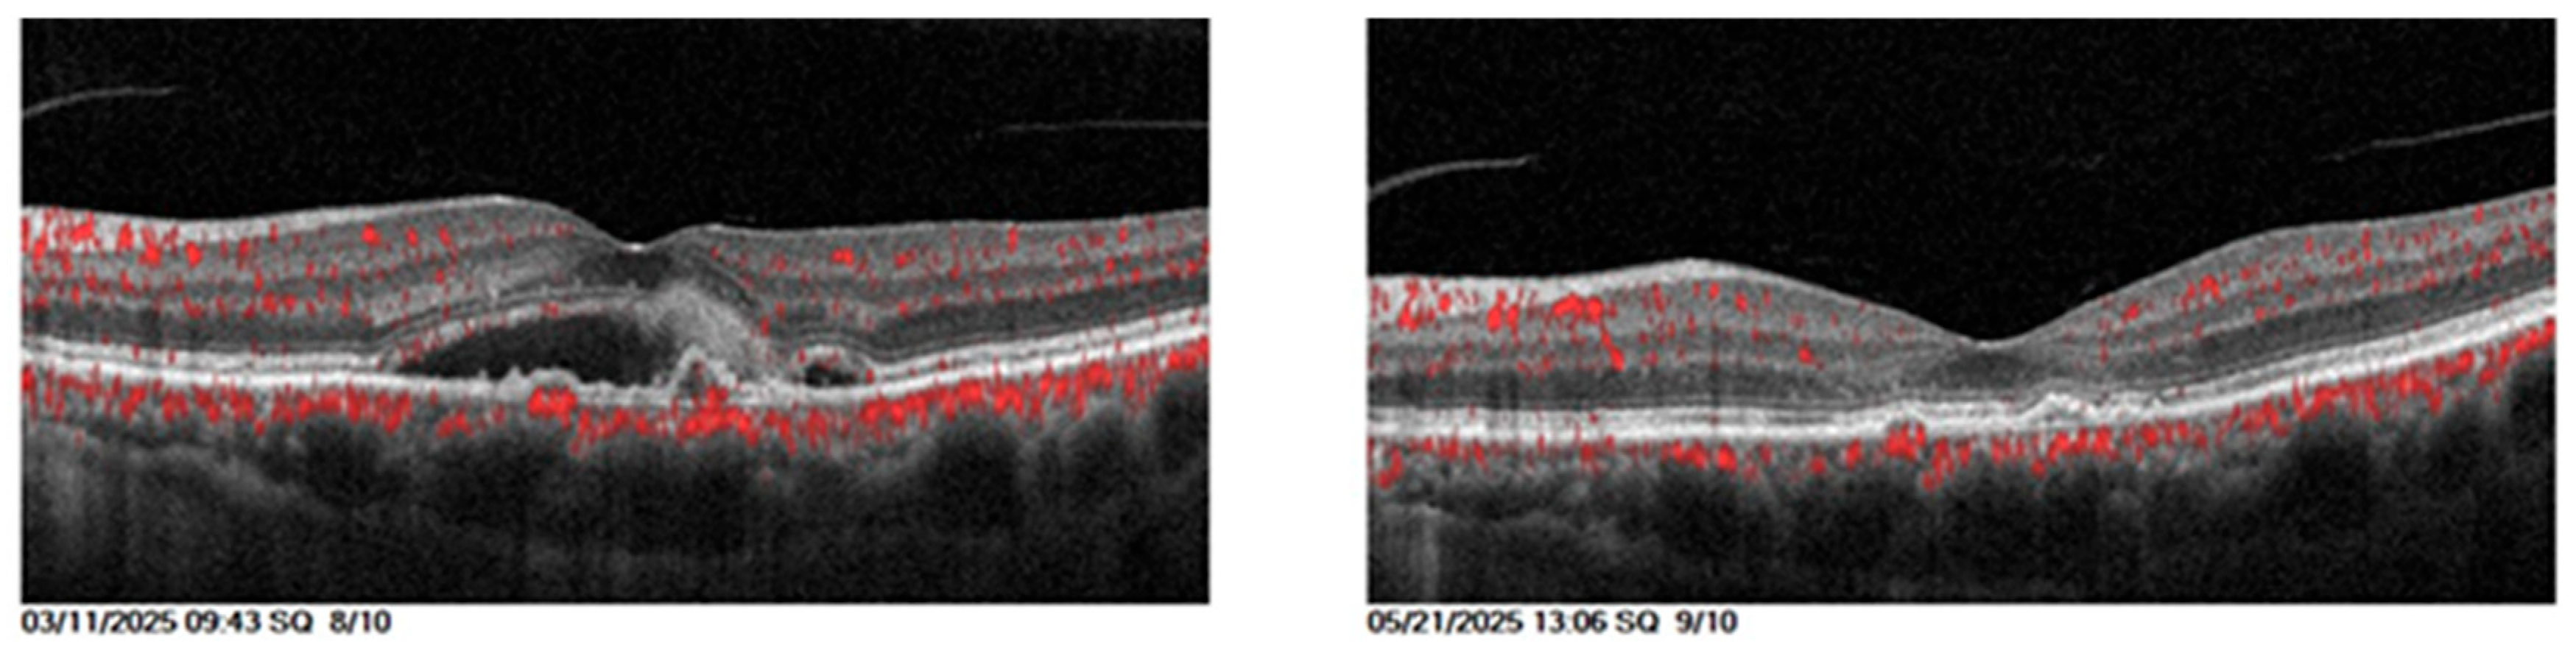

The comparison of clinical parameters before and after starting Faricimab was detailed in Table 5. Example on the anatomical outcome showed in Figure 5.

Visual acuity and central retinal thickness show a significant improvement (P<0.001). The mean visual acuity reduced from 0.60 (SD±0.24) to 0.44 (SD±0.24) and mean central retinal thickness reduced from 464.74 (SD±112.99) to 288.5 (SD±85.04), 1 month after the third faricimab injection.

Intraretinal fluid and subretinal fluid show significant reduction (P<0.001). The proportion of eyes with SRF decreased from 15 (32.60%) pretreatment to 2 (4.34%) posttreatment, while the proportion of eyes with IRF decreased from 46 (100%) to 19 (41.30%). Intraocular pressure remained stable over the course of the study (p=0.673).

Figure 5. 68-year-old female with diabetic macular edema with previous five intravitreal aflibercept injections with persistent CMO and IRF, and after three loading doses of Faricimab, the retina was dry, and visual acuity improved from 1 to 0.6.